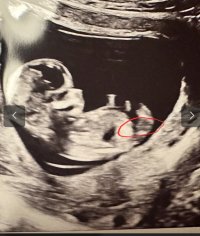

trodde kanskje det var noe ) se hvor jeg har satt ring på bildet hihi

? Er 13+1 her